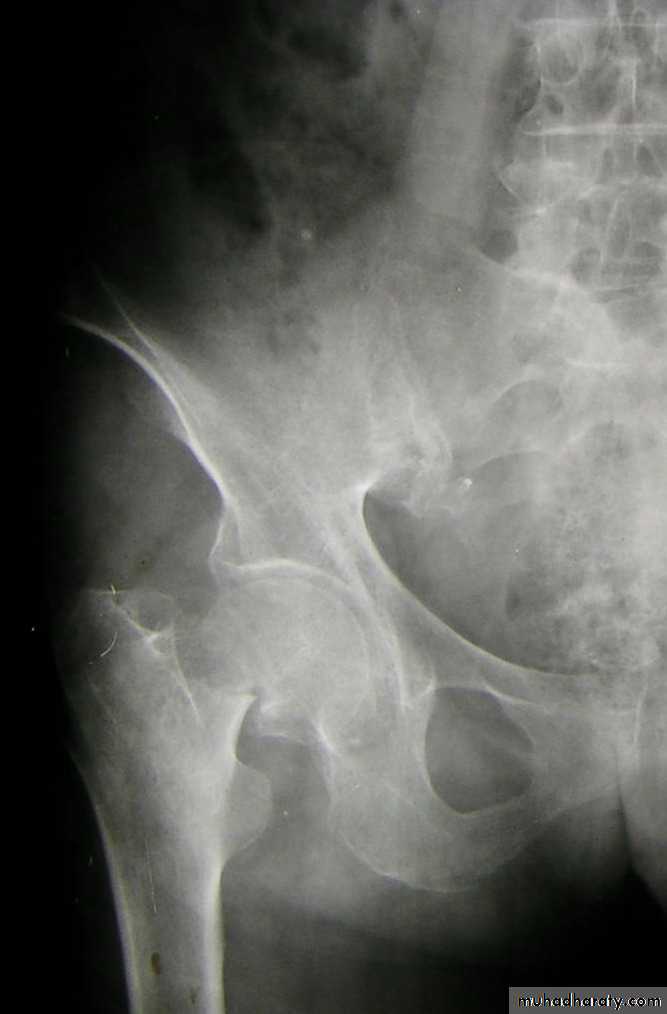

Posterior dislocation:

Mechanism of injure:4 out of 5 traumatic hip dislocations are posterior.

Usually occur in road traffic accident when the knee striking the dashboard

the femoral head is forced out of its socket sometimes associated with fracture.

The golden role is to x ray the pelvis in every case of sever injure

and with femoral fracture to include both the hip and knee.Radiological examinations

X-R AP view we can see the dislocation with or without associated fracture posterior wall of the acetabulum,or fracture head of the femur,

And neck of femur.